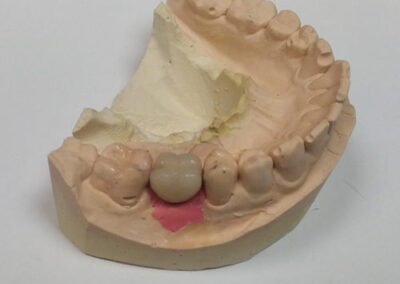

Pacijentu je nedostajao prvi molar u bočnoj regiji. Ovaj zub je posebno značajan i njegov nedostatak narušava kontinuitet celog zubnog luka. Imajući u vidu da su susedni zubi bili zdravi, kao idealno rešenje sa pacijentom je dogovorena ugradnja implanta i protetska nadoknada na implantu.

Na rendgen snimcima prikazana je donja vilica pre ugradnje implanta i donja vilica nakon perioda srastanja (oseointegracije) implanta sa koštanim tkivom.